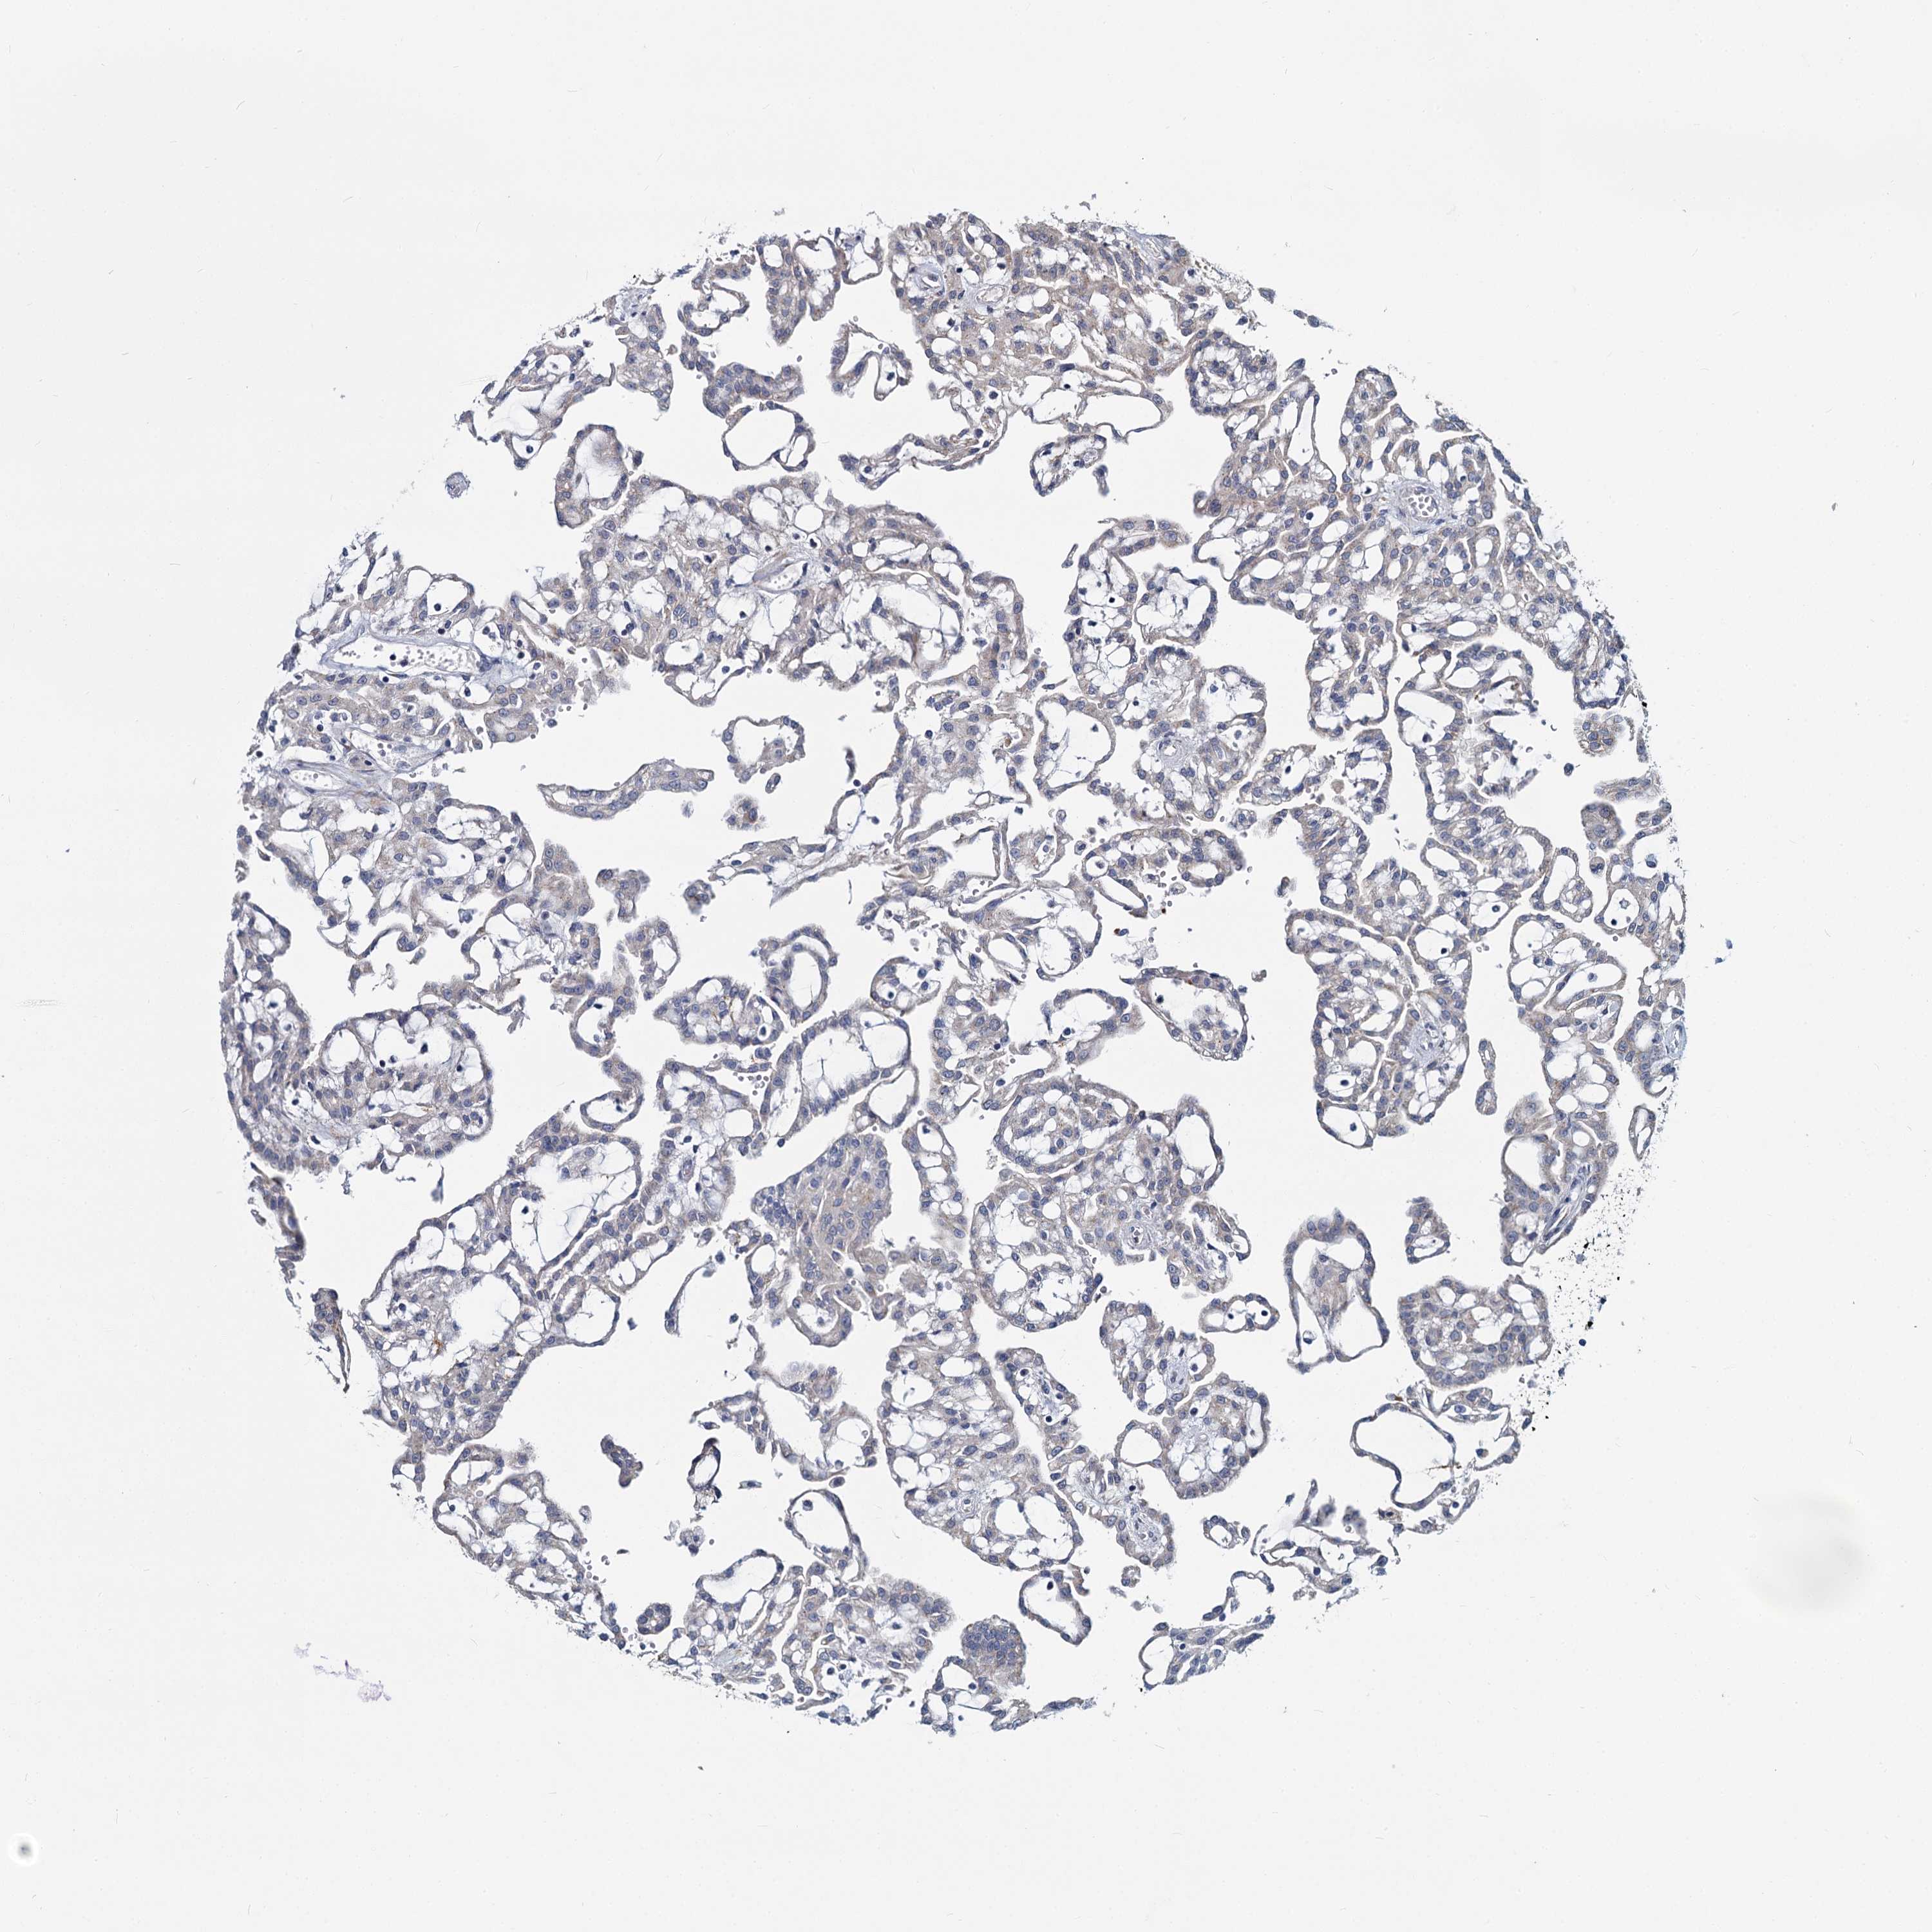

CANCER RENAL CANCER Show tissue menu

KICH TCGA KIRC TCGA KIRC VALIDATION KIRP TCGA PROTEIN RCC CPTAC PROTEIN EXPRESSION

KIDNEY RENAL PAPILLARY CELL CARCINOMA (TCGA) - Interactive survival scatter ploti

DCUN1D2 is not prognostic in Kidney Renal Papillary Cell Carcinoma (TCGA)